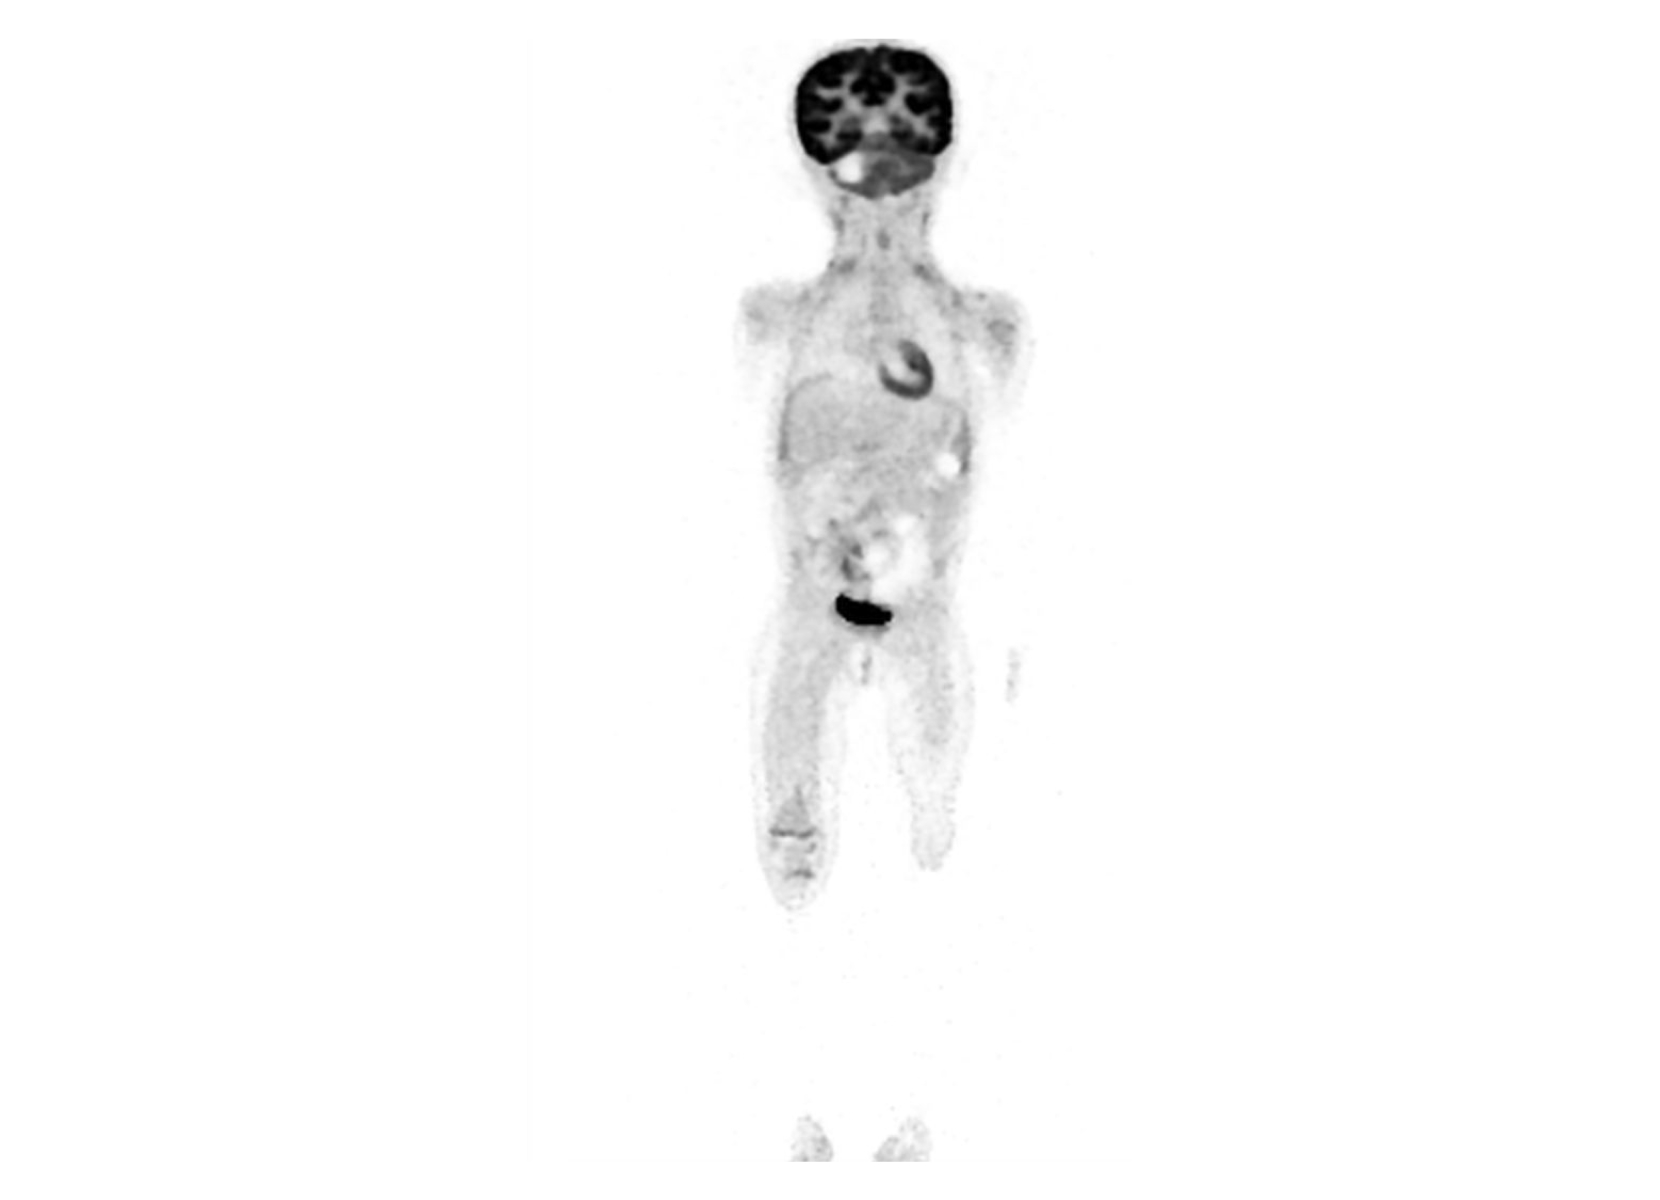

ANY Scanner

SubtleEDGE

PACS/Workstation

Reading